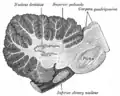

Section of the medulla oblongata at about the middle of the olive. -

Ele consiste numa lâmina cinzenta dobrada na forma de uma capsula incompleta, abrindo-se medialmente por uma abertura chamada de hilo.

Fibras olivocerebelares são neurônios que possuem seus corpos celulares no núcleo olivar inferior.[7] Seus axônios deixam o núcleo medialmente, pelo hiilo, atravessando a linha média e ascendendo ao cerebelo pelo pedúnculo cerebelar inferior[7] Uma vez que eles adentram o cerebelo, elas são denominadas como fibras trepadeiras.[7] Finalmente, elas fazem sinapses no córtex cerebelar, incluindo o córtex do vermis, do lóbulo paramediano e nos hemisférios cerebelares.[7]

As fibras que deixam a oliva inferior no hilo podem ser referidas como o "pedúnculo" da oliva. Eles cruzam com aqueles da oliva oposta na rafe. Após a rafe, elas podem ser referidas como fibras internas arqueadas.